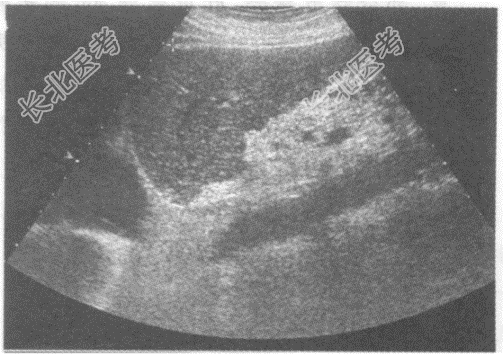

- 单项选择题临床资料:男性患者, 62岁,自述右上腹不适, 持续性隐痛;乙型肝炎病史20年, 胃镜发现食道静脉曲张。

超声综合描述:肝回声明显不均, 有结节感,三支肝静脉变细, 肝中裂增宽,门静脉内径1.4cm; 脾厚4.8cm,脾长径14.7cm。

超声提示: A、慢性酒精中毒性肝病门静脉增宽脾大

B、肝弥漫性肝癌门静脉增宽脾大

C、肝硬化门静脉增宽脾大

D、先天性肝纤维化门静脉增宽脾大

E、肝脓肿门静脉增宽脾大